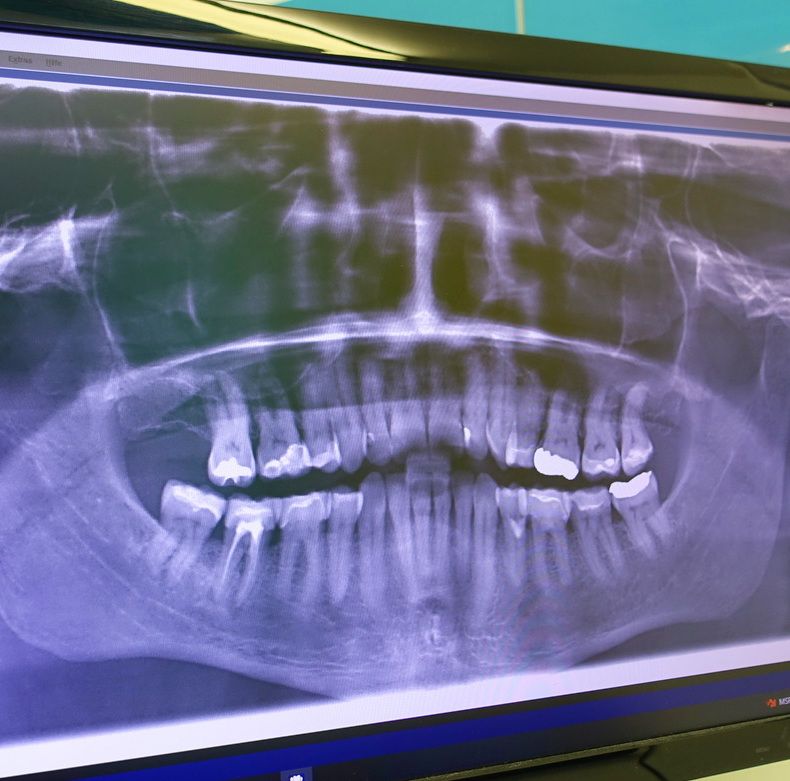

Das digitale Röntgen ist eine moderne bildgebende Technologie in der Zahnmedizin, die es ermöglicht, hochauflösende Röntgenbilder mit reduzierter Strahlenbelastung aufzunehmen. Es ersetzt herkömmliche analoge Röntgensysteme und bietet zahlreiche Vorteile für die Diagnostik und Patientenversorgung.

• Intraorale und extraorale Aufnahmen: Einzelzahnaufnahmen, Panoramaaufnahmen (OPG) und digitale Volumentomographie (DVT).

• Schnelle Bildverfügbarkeit: Sofortige Darstellung der Röntgenbilder auf dem Bildschirm ohne chemische Entwicklung.

• Hohe Bildqualität: Optimierte Kontraste und Detailgenauigkeit für eine präzisere Diagnose.